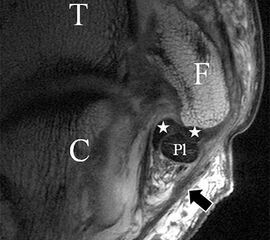

Die Definition der Dehiszenz und Lage möglicher Banddislokationen mit gelenkinterponierenden oder nach lateral umgeschlagenen Bandanteilen (Abb. 6 a und b) oder Darstellung knöcherner Ausrisse (Abb. 7), leisten einen wichtigen Beitrag zur weiteren Therapieplanung. Auch assoziierte Verletzungen der Kapsel sind normalerweise klar abgrenzbar (Abb. 6 c). Im Rahmen reparativer Prozesse und als Ausdruck einer persistierenden Stressreaktion entwickeln sich häufig synoviale oder fibrotische Meniskoide. Auch diese sind in hochauflösender Technik, ohne die Durchführung einer direkten MR-Angiographie, nachweisbar und in ihrer Ausdehnung klar zu dokumentieren (Abb. 8).

Der Ursprung des Ligamentum fibulocalcaneare liegt unmittelbar kaudal und dorsal des Ursprungs des Ligamentum fibulotalare anterius, so dass gehäuft kombinierte Verletzungen und auch ein gemeinsamer knöcherner Ausriss beobachtet werden. Nach kaudal dorsal verläuft das Band dann nach medial konvex unter die Peroneussehnen. Danach ist ein schräg deszendierender, gestreckter Verlauf bis zum calcanearen Ansatz abgrenzbar (Abb. 10). Dieser zu allen drei Standardebenen schräge Verlauf erschwert häufig die Diagnostik des LFC vor allem bei subtileren Verletzungen. Spezialprojektionen, die dem Bandverlauf orthograd folgen (entweder schräg coronar oder schräg sagittal) erleichtern auch hier die Diagnostik (Abb. 11) insbesondere nicht dislozierter Avulsionen. Assoziierte Verletzungen der Peroneussehnenloge müssen mit beurteilt werden, wobei neben Verletzungen der Sehnen und Sehnenscheiden die Beurteilung des Retinaculum peroneum superius und inferius wichtig ist. In einem Kollektiv von Patienten mit chronischen Außenbandinstabilitäten weisen 50% der Patienten eine Verletzung dieser Strukturen auf 5. Auch hier erleichtern hochauflösende Techniken die Diagnostik (Abb. 12).